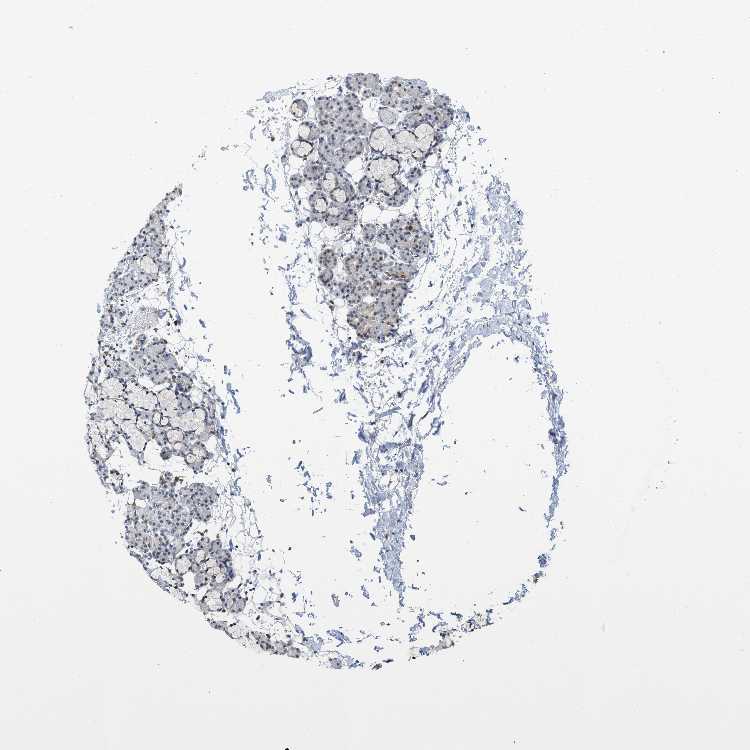

SALIVARY GLAND - Antibody stainingi

Antibody staining in the annotated cell types in the current human tissue is reported as not detected, low, medium, or high, based on conventional immunohistochemistry profiling in selected tissues. This score is based on the combination of the staining intensity and fraction of stained cells.

Each image is clickable and will lead to virtual microscopy that enables deeper exploration of all samples and also displays staining intensity scores, fraction scores and subcellular localization as well as patient and tissue information for each sample.

Antibody HPA019535

Glandular cells Not detected